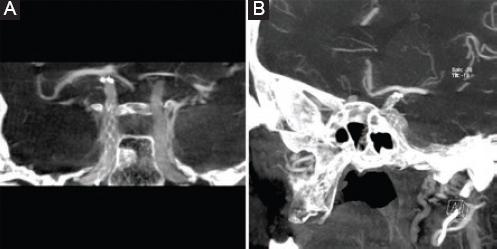

La paciente recuperó la función completa del III nervio craneal izquierdo a los 2 meses. En el seguimiento con estudio de DynaCT observamos la exclusión del aneurisma a los 3 meses (Fig. 3). Se manejó con antiagregación oral dual (ácido acetilsalicílico 100 mg y clopidogrel 75 mg cada 24 horas) por 3 meses y continuó con antiagregación oral única (ácido acetilsalicílico 100 mg cada 24 horas).

Las evaluaciones subsecuentes de las endoprótesis intracraneales siguen siendo un desafío. El estudio DynaCT es la mejor modalidad para evaluar la permeabilidad luminal de los vasos intracraneales tras la colocación de una endoprótesis; se observan menos artefactos y permite visualizar el lumen de las endoprótesis en vasos muy pequeños intracraneales (> 3 mm)19-22.